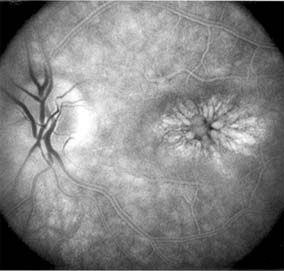

Presumed Ocular Histoplasmosis Syndrome (Figures 10-5, 10-6 and 10-7)

In this disease, serous and hemorrhagic detachments of the macula are associated with multiple peripheral atrophic chorioretinal scars and peripapillary chorioretinal scarring (see Chapter 7). The syndrome usually occurs in healthy patients between the third and sixth decades of life, and the scars are probably caused by an antecedent subclinical systemic infection with Histoplasma capsulatum. The macular detachments are due to subretinal neovascularization, and the visual prognosis depends on the proximity of the neovascular membrane to the center of the fovea. If the membrane extends inside the foveal avascular zone, only 15% of eyes will retain 20/40 vision. A macular scar may change over time, and 10% of patients with normal maculae will develop new atrophic scars in this region. The relative risk of developing macular subretinal neovascularization in the second eye of an affected patient is significant, and these patients should be instructed in the frequent use of the Amsler grid and the importance of prompt examination when changes are detected.

Figure 10-5

Figure 10-5: Presumed ocular histoplasmosis syndrome with active disease (large arrows) and an inactive pigmented macular scar (small arrow). Peripapillary pigmentation (curved arrow) is also present.

Figure 10-6

Figure 10-6: The early fluorescein angiogram shows an inactive hypofluorescent scar (small arrow) and the characteristic lacy hyperfluorescence of subretinal neovascularization (open arrows).

Figure 10-7

Figure 10-7: Late fluorescein leakage from macular subretinal neovascularization in a patient with presumed ocular histoplasmosis syndrome.